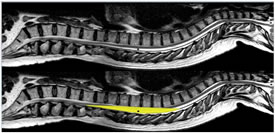

The name segmental spinal is often widely used synonymously with thoracic spinal anaesthesia. But in real sense segmental spinal anaesthesia means “Blocking of the required dermatomes essential for the proposed surgical procedure with very low effective local anesthetic drug dose.” This often necessitates dural puncture at high lumber or thoracic levels apart from the conventional spinal below L1. Lower the dose of local anesthetic drug used more likely it is to produce a true segmental block1. There are three main issues related to spinal at unconventional levels risk of neuronal injury, respiratory embarrassment due to extensive thoracic nerve blockade and cephalad spread of local anesthetic drugs causing high or total block2. Many studies performed using myelography showed that the thoracic cord lies anteriorly in theca while lumber spinal cord is situated more dorsally. The space between the dura mater and the mid to lower thoracic spinal cord on its width is actually greater than that of epidural space in lumber region because of lumber enlargement. So lumber spine is at greater risk of needle damage3. A possible anatomical explanation for the absence of spinal cord lesion during the accidental perforation of thoracic dura mater was proposed by Imbelloni and Gouveia through a study using MRI - which showed following measurements:- 5.2mm at T2, 7.75mm at T5 , and 5.88mm at T10 , a space sufficiently large to allow the entrance of a needle during accidental or intentional puncture of the dura4.

Figure 1: MRI Image of Spinal Cord- Note sufficiently large space at thoracic level